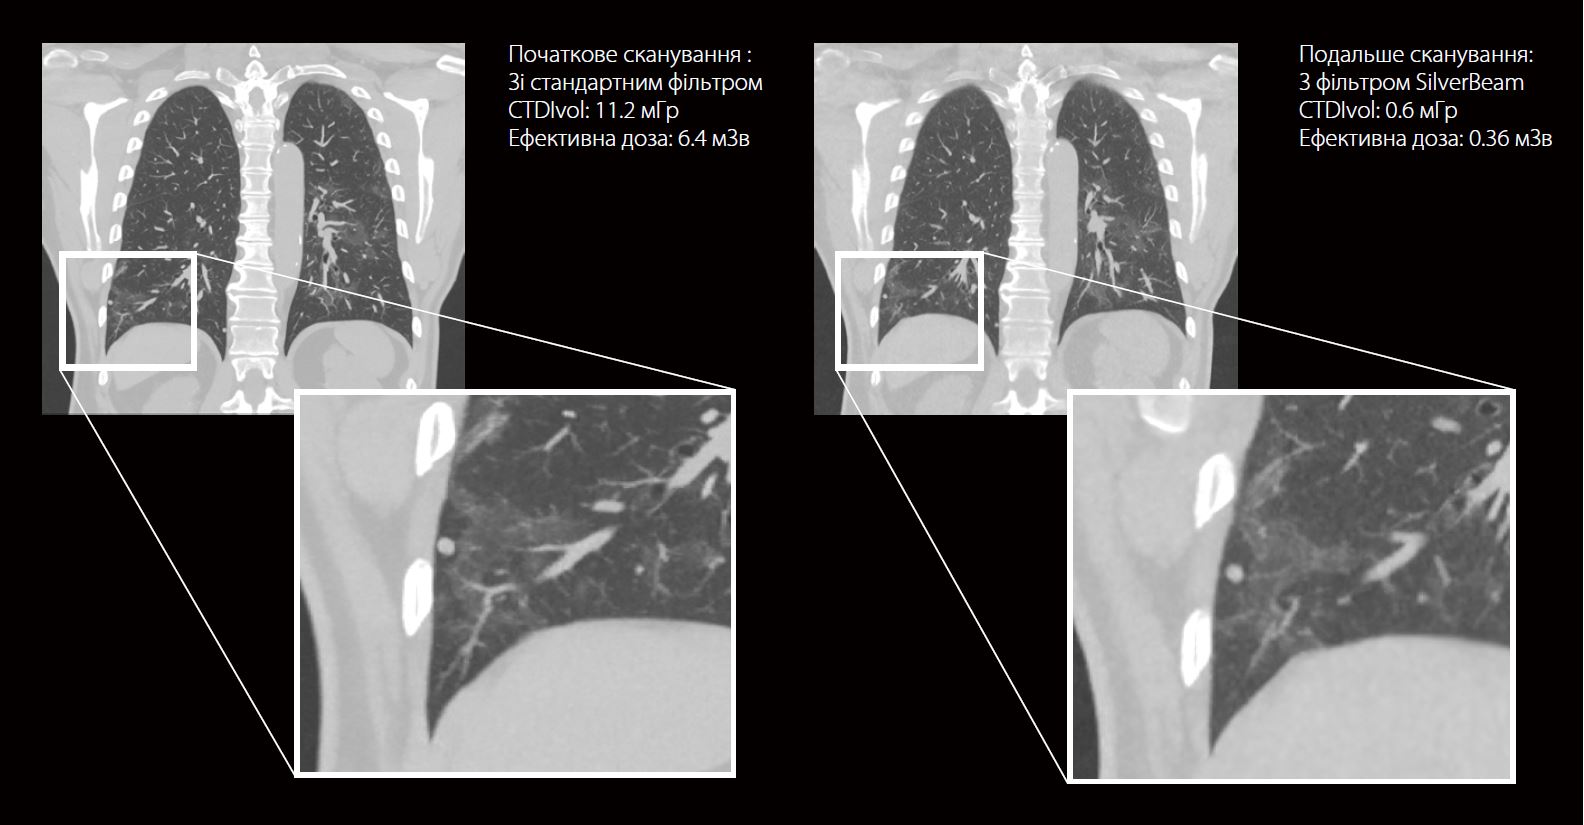

Початкове сканування проводили з дозою опромінення 6,4 мЗв з використанням стандартного фільтра. Подальше сканування було виконано за допомогою фільтра SilverBeam і в результаті було отримано дозу опромінення 0,36 мЗв. Обидва скани були реконструйовані за допомогою Advanced intelligent Clear-IQ Engine (AiCE). Якість зображення сканування SilverBeam порівнянна зі скануванням зі стандартним фільтром, але зі значно меншою дозою опромінення. Легеневий вузлик не збільшився в розмірах. Було рекомендовано повторне сканування низькими дозами через 3 місяці.

Стандартна КТ грудної клітки

Експозиція: 120 кВ, SUREExposure

Швидкість ротації: 0.5 сек.

Тех. зниження дози: AiCE

CTDI vol: 11.2 мГр

DLP: 455.8 мГр. cм 6.4

Ефективна доза: мЗв

КТ грудної клітки з SilverBeam

Експозиція: 120 кВ, 80 мA

CTDI vol: 0.6 мГр

DLP: 25.7 мГр. см

Ефективна доза: 0.36 мЗв

Фільтр SilverBeam у поєднанні з AiCE забезпечує високоякісні зображення легень у дозі, ближчій до рентгенографії грудної клітки. У цьому випадку було досягнуто зменшення дози на 94% для сканування SilverBeam порівняно з початковим скануванням зі стандартним фільтром, зберігаючи клінічну візуалізацію вузликів.